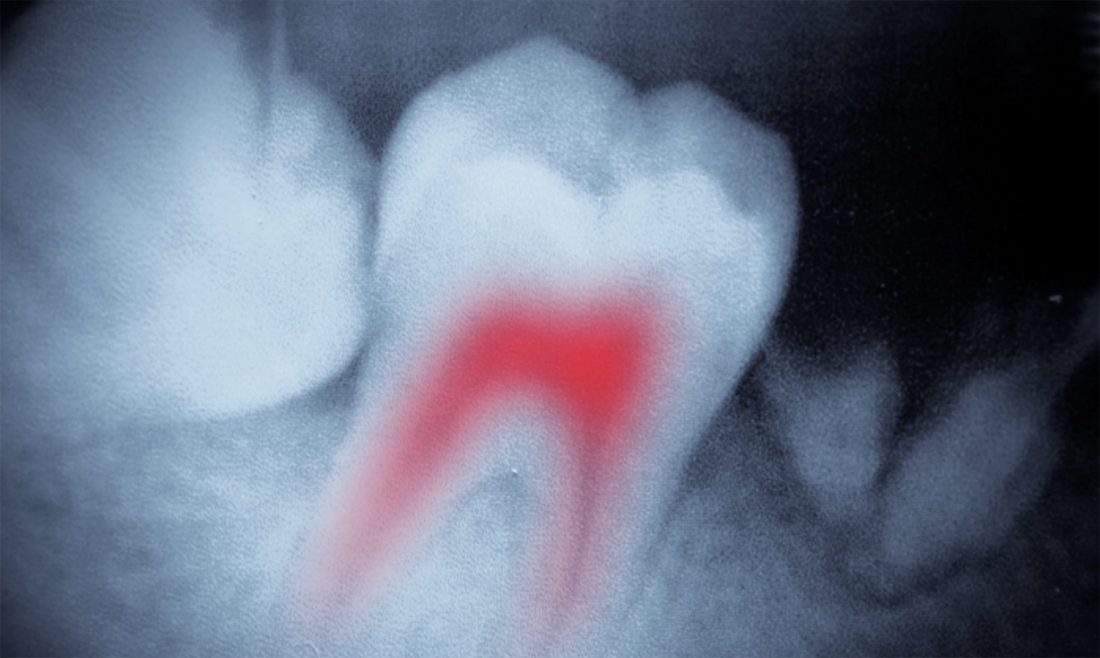

The Anatomy of a Root Canal

During a root canal procedure, the infected pulp tissue—which contains nerves and blood vessels—is removed to alleviate pain and prevent the spread of infection. This process allows the patient to retain the tooth in their mouth, maintaining its functional role in chewing and aesthetics. However, once the tooth's living tissue is removed, it effectively becomes a dead entity within the jawbone [1].

A healthy tooth can usually defend itself against bacterial invasion through its intact immune response and a fluid flow that pushes bacteria outward. In contrast, a root canal-treated tooth lacks these natural defenses, making it a potential reservoir for bacteria and toxins. These bacteria are hidden from the body’s immune system and continuously release toxins into the bloodstream [2].